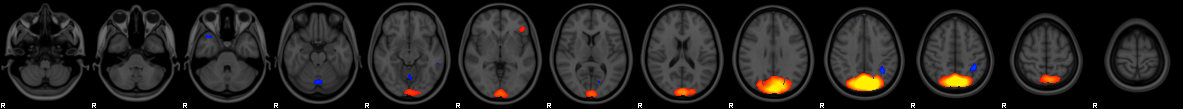

Component #53

Prior:

10% weight

Thickness

:

4% weight

Area

0% weight

VBM

87% weight